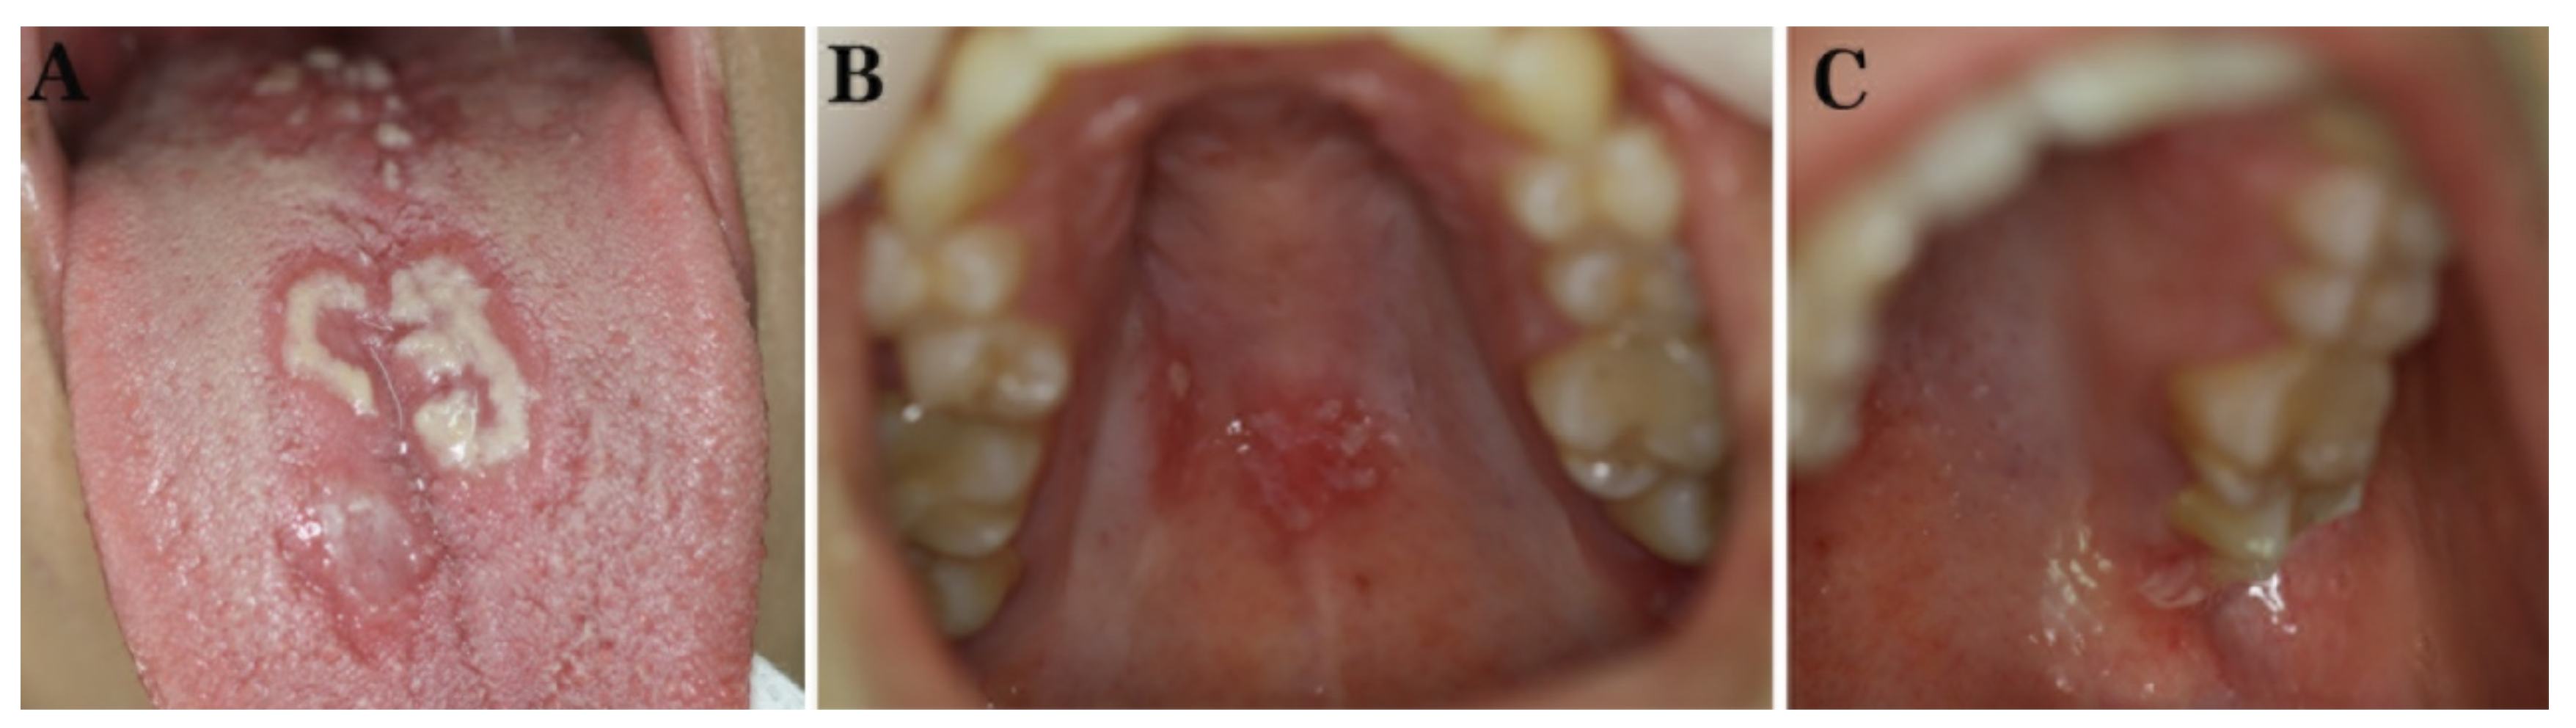

2.1. Case 1

2.2. Case 2

2.3. Case 3